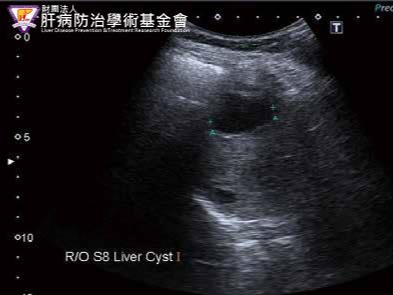

- 간 낭종